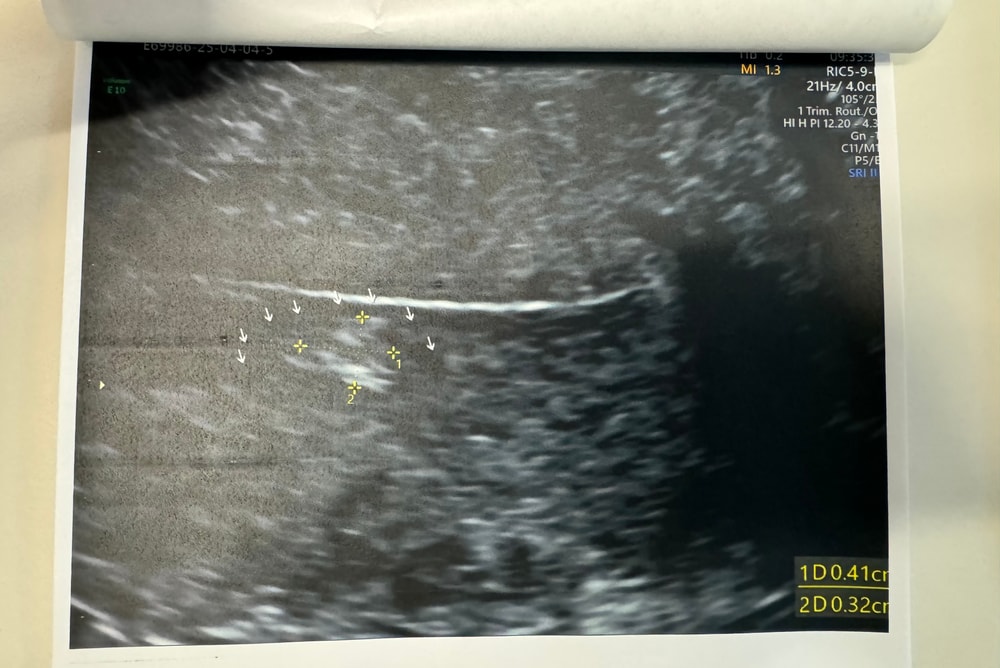

Полип?

На 21 дц полип видно не будет

Толстый Карлсон, о боже.. кто вам эту ерунду говорит? Надеюсь не врач, потому что тогда понятно почему он предположил полип на 21 дц Полипы смотрят на 5-7 дц и не просто так В не в рандомный день еще и по середине цикла

Толстый Карлсон, да действительно все образования лучше видны сразу после месячных на 4-5 день цикла. У меня тоже небыло ничего, а на следующий месяц уже полип 2*1, 6 см. Увидили на 16 день цикла, и сказали переделать УЗИ на 4 день цикла, переделала УЗИ подтвердили полип.